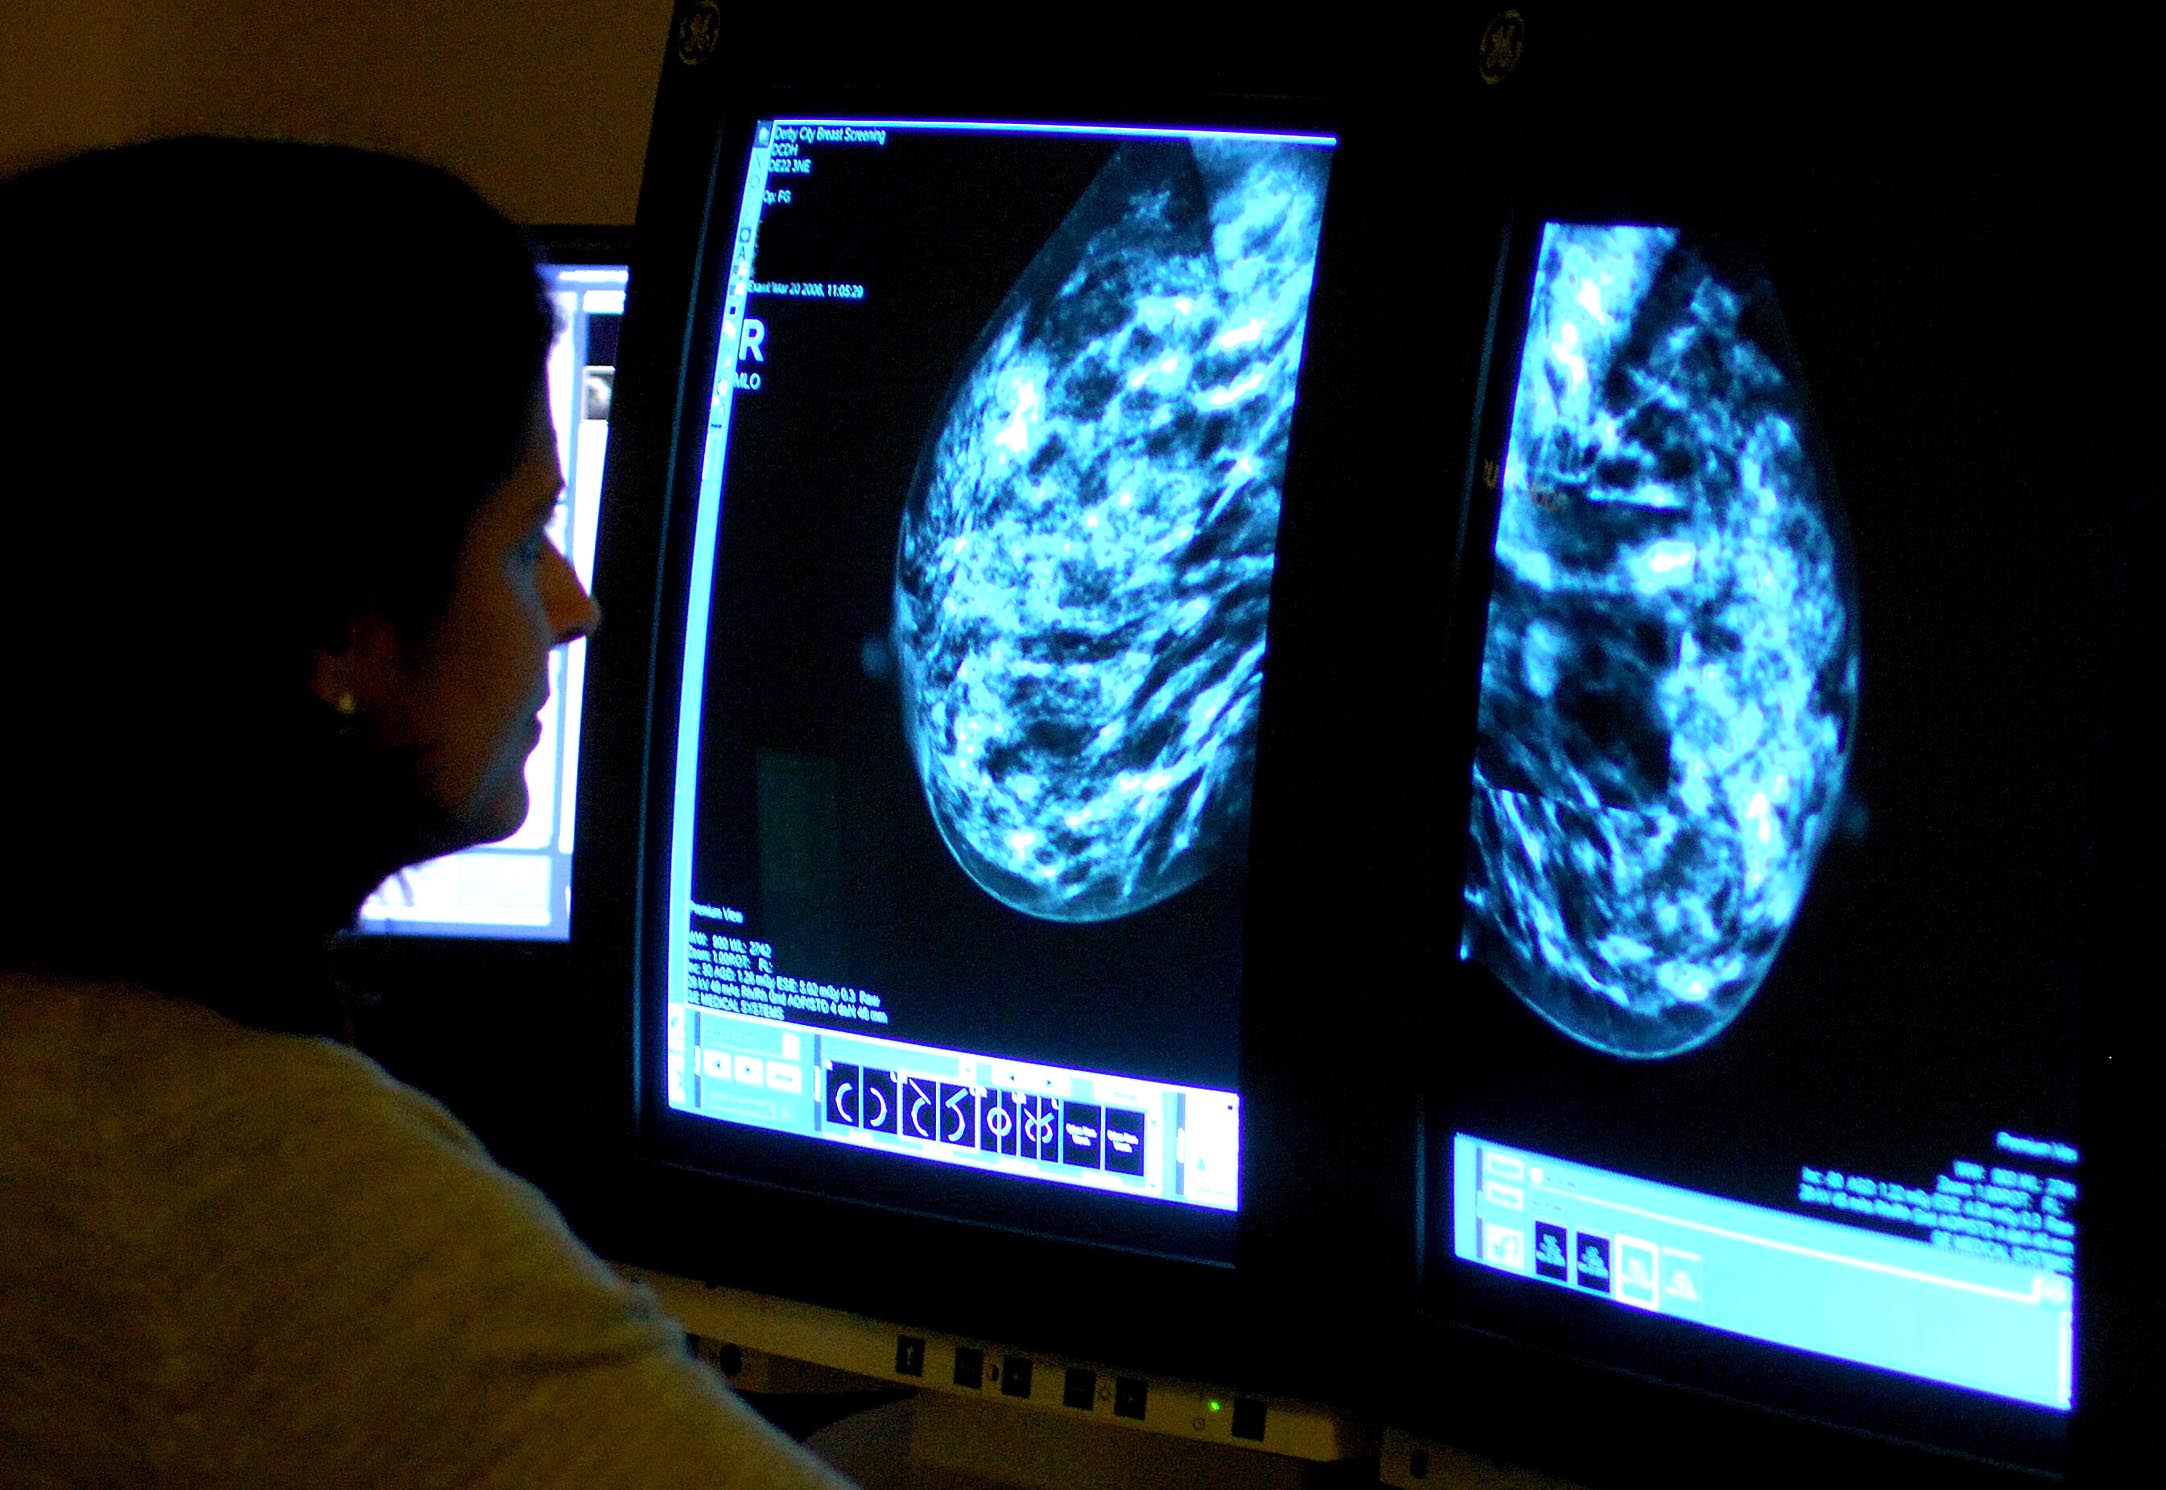

More women in Hampshire have received breast cancer screenings, new figures show.

A breast cancer charity has welcomed the increasing breast screening uptake across England, but warned there remains "significant work to do to save more lives".

The rise follows NHS England’s first-ever breast screening awareness campaign to encourage more women to attend potentially life-saving mammographies in order to help detect cancers earlier.

NHS England figures show 135,709 women aged between 53 and 71 in Hampshire underwent a breast screening in the three years to March – up from 127,910 in the three years to March 2023.

It means 77.3% of eligible women in the area were screened over the last three years – up from 73.9% between 2020-21 and 2022-23.